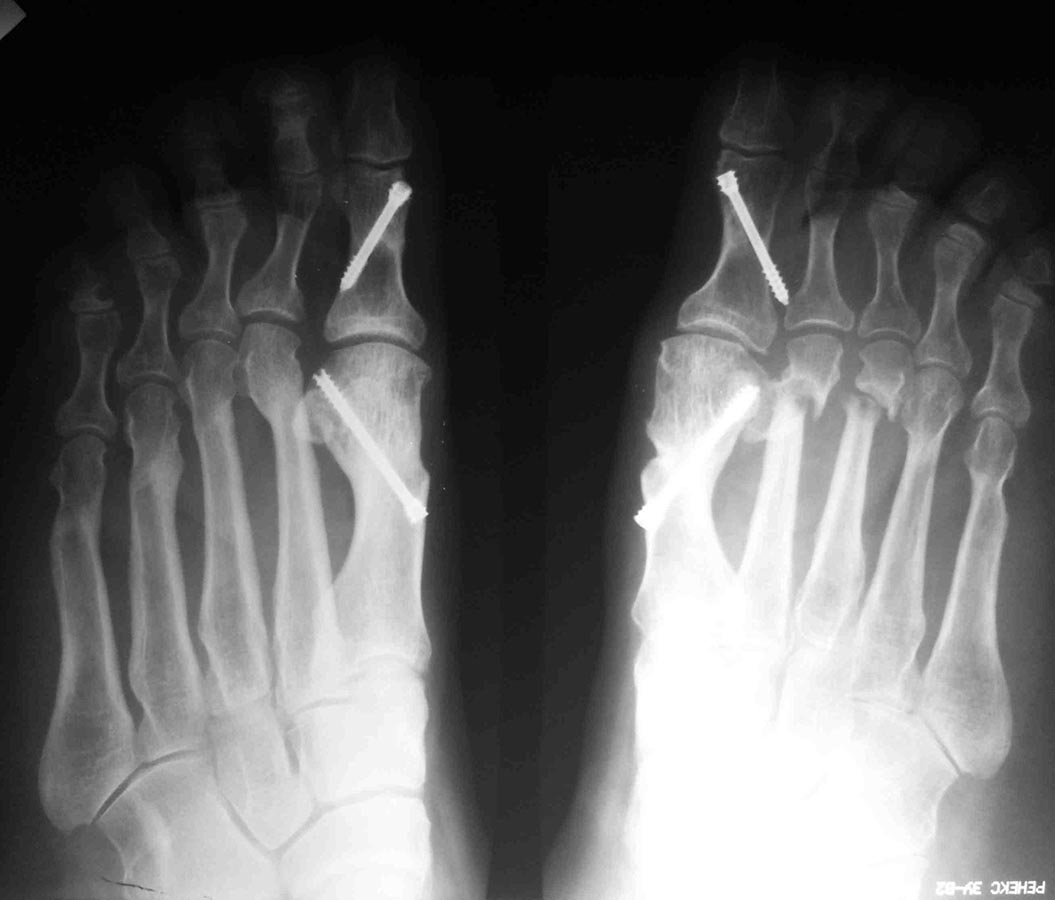

Уважаемые коллеги, я понимаю, что уже утомил вас оперированными стопами, но помогите еще с одним случаем Женщина около 50, активная, оперирована 1 год назад. Тип остеотомии в выписке не указан (похоже с 1-го по 5-ую + фаланги). Сожалею. что фото стопы не удалось выложить, клинически - выраженная девиация всех пальцев стопы слева. Что предпринять? Латеральный релиз, утягивание (лучшего синонима не нашел) медиальной капсулы+остеотомии 4-5 с нормальной повязкой? 1-ый луч - SERI (для жесткости остальных- к нему притянуть), но, головка и так скомпроментирована (или это не брать в расчет?)+ освежение ложняков+ коррегирующая остеотомия 4-5 Weil с фиксацией винтом (или без фиксации?). С фалангами что делать? Кажется, что ничего?

А чего Вы притесняетесь? Насчет "утомил вас оперированными стопами". Такая же ортопедия, как и вся остальная, обсуждаемая на форуме. Да еще сложный ревизионный случай. Изначально то все здорово было. Так бывает, к сожалению, когда все вроде правильно сделано, а в результате не складывается. Почему-то 2 из 10 плюсневых не срослись. На прошлогодней конференции AOFAS был доклад о неудачах после операций на стопе, в котором авторы выделили группу «нестрастальщиков»: пациентов, которые не срастаются без очевидных причин для этого. Может и здесь подобный случай. Из предложенного Вами плана не ясно, зачем делать SERI? Ее ведь сделали год назад. Только не стандартный вариант с фиксацией спицей, а более сложный, с внутренней фиксацией. Возможно, в этом была причина избыточной латерализации головок: подошвенные пластинки 1 и 2 плюснефаланговых суставов тесно связаны. Слишком радикальное уменьшение первого межплюсневого угла за счет латерального смещения головки первой плюсневой привело к дестабилизации нефиксированных остеотомий 2 и 3 плюсневых. И если сейчас еще больше переместить головку первой плюсневой кнаружи, это только усугубит ситуацию. На схеме я показал, в каком положении окажутся 2 и 3 пальцы в случае репозиции головок их плюсневых: расстояния между 1 и 2 лучами итак практически не остается. Я бы в данном случае подровнял внутренний контур головки 1 плюсневой, удалил винт из основной фаланги, выполнил латеральный релиз 1 плюснефалангового, эйкиноподобную остеотомию основной фаланги 1 пальца; репозицию головок 2-3 плюсневых с фиксацией их головок спицами на 4-6 недель и положив в область ложных суставов костную аутостружку или какой-нибудь искусственный заменитель кости. Если при этом пальцы не станут ровнее – выполнил бы остеотомии основных фаланг соответствующих пальцев. Без вмешательства на 4-5 плюсневых.